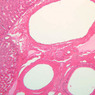

Examine the H&E-stained sections of liver (slides B-29 [10x, 20x, 40x-labeled] [2.5x-labeled, 10x, 20x, 40x] [10x-labeled, 20x, 40x-labeled] and B-30 [2.5x, 10x-labeled, 20x]). At low power, identify the connective tissue capsule (Glisson’s capsule), central veins and portal triads (portal canals). Note that the cells of the liver parenchyma (hepatocytes) appear as cords--more accurately, plates--of cells that radiate out from the central veins and partially enclose blood spaces known as hepatic sinusoids. Note that the plates of hepatocytes appear to branch and fuse and that, as a rule, they are only one or two cells thick. Do you see any binucleate hepatocytes?

Using the 10X (B-29, B-30)and 40X (B-29) objectives, examine several portal triads, noting the variable number of profiles of hepatic artery, portal vein and bile duct that comprise the portal triad. Near the boundary between adjacent lobules, try to find some of the small elements of the bile duct system known as canals of Hering.

Using the high dry objective, study the lining of the central vein and hepatic sinusoids (B-29). In some places the hepatocytes are exposed directly to the sinusoidal lumen, but, as a rule, there is a basal lamina which supports a discontinuous mosaic of endothelial cells and specialized phagocytic cells known as Kupffer cells. Find examples of Kupffer cells and endothelial cell nuclei. Note that in some places you may see a narrow space (the space of Disse) between hepatocytes and the basement membrane underlying endothelial and Kupffer cells. Using the oil immersion (100X) objective, look very carefully along the boundaries between adjacent hepatocytes to see if you can find a bile canaliculus--the most delicate portion of the bile duct system--the walls of which are formed by the plasma membranes of adjacent hepatocytes.